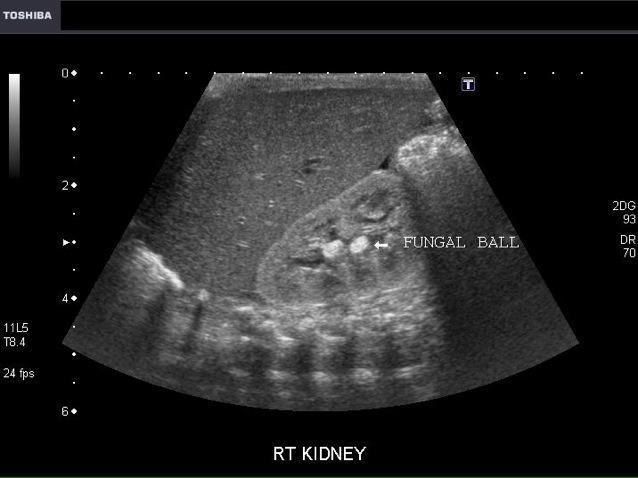

Mycetoma (fungal ball)

candidiasis is the most common

Non shadowing hyperechoic mass